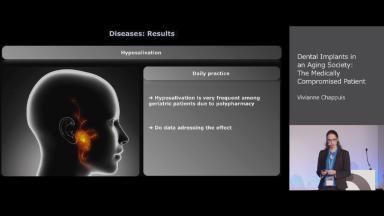

Dental Implants in an Aging Society: The Medically Compromised Patient

This lecture summarizes the findings of the 6th ITI Consensus Conference on medication-related implant failure in aging populations. It addresses the impact of disabling systemic diseases in an aging society and the related intake of medications on implant rehabilitation. Implant survival and failure rates are discussed, and the lecture concludes with an overview of diseases and medications and their effect on implant survival rates.

- discuss the effect of systemic diseases in aging populations on implant survival rates

- describe the effect of diseases such as e.g. cardiovascular diseases on implant survival rates

- recognize the effect of cancer-related radiotherapy and radiation dose on implant survival rates

- explain the effect of regular intake of oral, intramuscular or intravenous medication affecting bone metabolism on implant failure